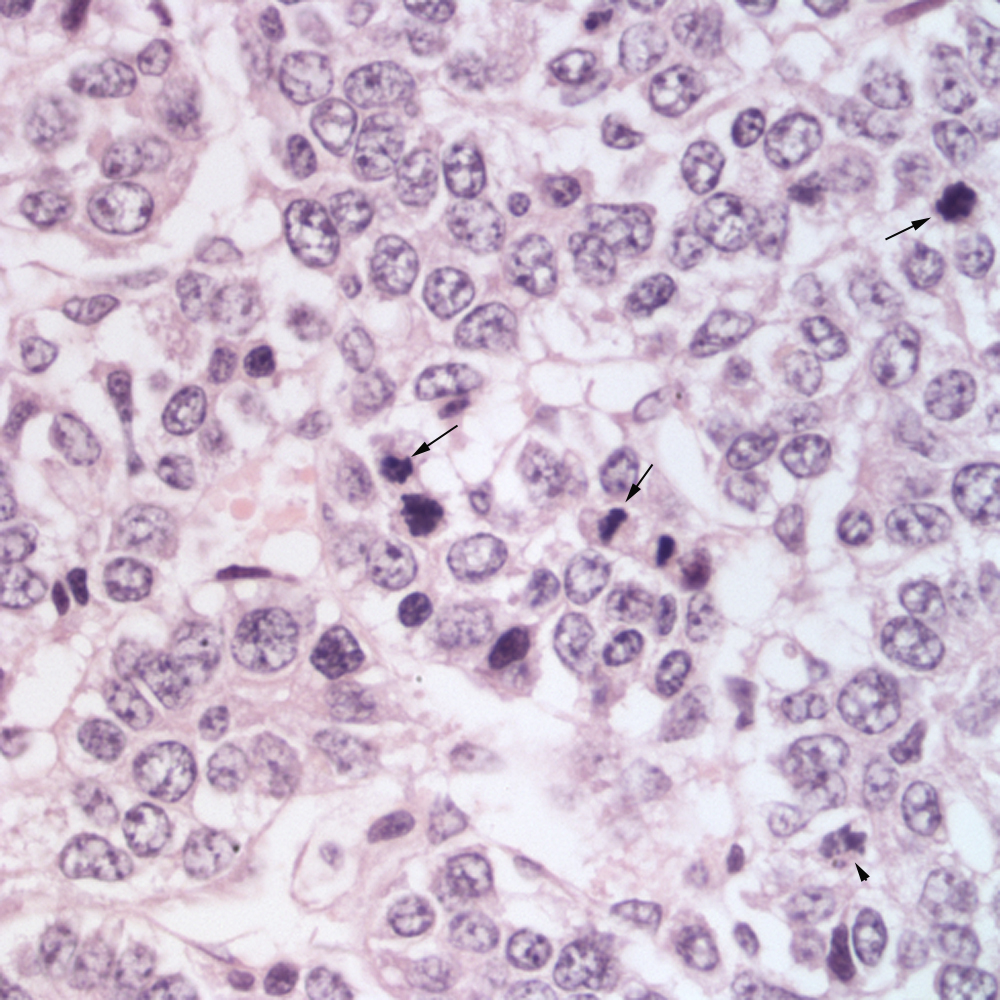

Figure 9 Histologic section of a liver mass in a horse eClinpath Horse Liver Tumor Equine liver disease was first reported in the literature in 1965 and there have been significant advances in our knowledge since that time. The research article is about a study that uncovers three new cases of primary liver tumors (specifically, hepatoblastoma and hepatocellular. [2] recognizing signs of liver disease, such as jaundice or behavioral changes, is key to early intervention.. Horse Liver Tumor.

Figure 8 Histologic section of a liver mass in a horse eClinpath Horse Liver Tumor [2] recognizing signs of liver disease, such as jaundice or behavioral changes, is key to early intervention. Equine liver disease was first reported in the literature in 1965 and there have been significant advances in our knowledge since that time. Liver dysfunction in horses can arise from various causes, including exposure to toxins, infectious agents, inflammatory conditions, and other health. Horse Liver Tumor.